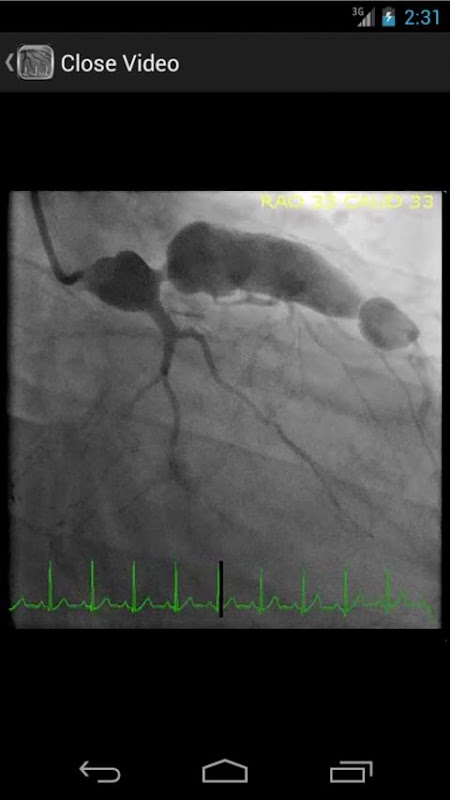

* Cơ sở dữ liệu có thể Tìm kiếm có chứa hơn 30 video (angiograms vành, ventriculograms, và aortograms) của cả hai phát hiện phổ biến và hiếm trong phòng thí nghiệm thông tim

CathSource cung cấp một cái nhìn tổng quan chi tiết về chủ đề thông tim và chụp động mạch quan trọng, kết hợp hình ảnh giáo dục / video cũng như các ý kiến của văn học y tế liên quan. CathSource là ứng dụng lý tưởng để hỗ trợ bạn trong sự hiểu biết và nhận ra bệnh lý tim mạch trong phòng thí nghiệm đặt ống thông.